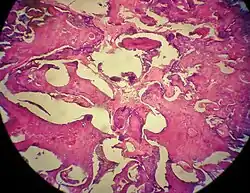

Histopathology

Odontomas are from mixed epithelial and mesenchymal components which are required for tooth development, producing enamel, dentine, cementum and pulp tissue. [6]